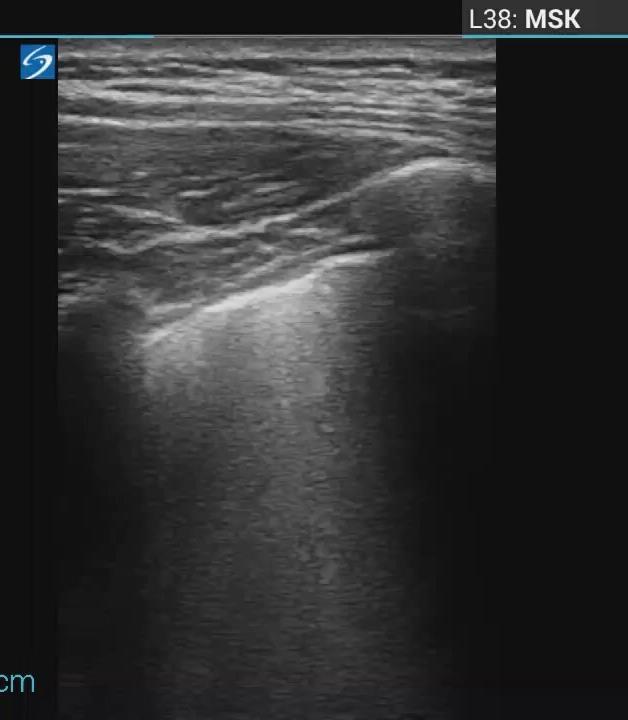

Pediatric COVID-19: MIS-C

Thoracic abnormalities

Cardiovascular abnormalities

Cardiomegaly

CHF or cardiogenic edema

Pulmonary parenchymal abnormalities

Lower lobe atelectasis

Bilateral opacities( ARDS)

Consolidation

Pleural abnormalities

Small pleural effusion

Mediastinal and hilar lymphadenopathy

Abdominal abnormalities

Solid viscera abnormalities

Hepatomegaly

Echogenic kidneys

Splenomegaly

Hollow viscera abnormalities

Gallbladder wall thickening

Bowel wall thickening

Bowel dilation

Gastric distention

Urinary bladder thickening

Peritoneal abnormalities

Small ascites

Mesenteric abnormalities

Mesenteric lymphadenopathy

• Gastrointestinal (GI) symptoms (abdominal pain, diarrhoea and vomiting) are prevalent in MIS-C

• Abdominal pain in 62%

• Up to 90% any GI symptom

• Anumber of studies have described abdominal imaging findings including ascites, bowel wall thickening and mesenteric lymphadenopathy